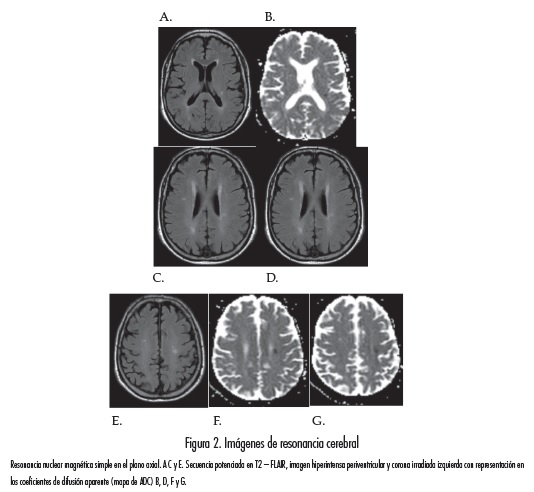

Al sexto día de hospitalización el paciente presentó otro episodio de déficit motor de hemicuerpo derecho, pero, en esta ocasión, con compromiso sensitivo ipsilateral que duró cuarenta minutos. Se decidió adicionar al régimen de anticoagulación acido-acetil salicílico, 100mg por día, y se repitió la resonancia magnética cerebral, la cual no mostró cambios con respecto a la previa (figura 2).

El último episodio lo presentó el octavo día. En este evento no hubo recuperación del déficit motor del hemicuerpo derecho, quedando con una hemiparesia fascio-braquio-crural densa. Una tercera RM cerebral (figura 3) mostró extensión de la lesión isquémica aguda en la corona radiada y múltiples lesiones isquémicas agudas en la región de la cápsula interna izquierda, no observadas previamente. Se inició proceso de rehabilitación y se continuó con la prevención secundaria con medidas antitrombóticas de anticoagulación, antiagregación y el manejo con estatina. El paciente permaneció estable, sin nuevos síntomas. Se dio de alta con el mismo tratamiento y rehabilitación integral.